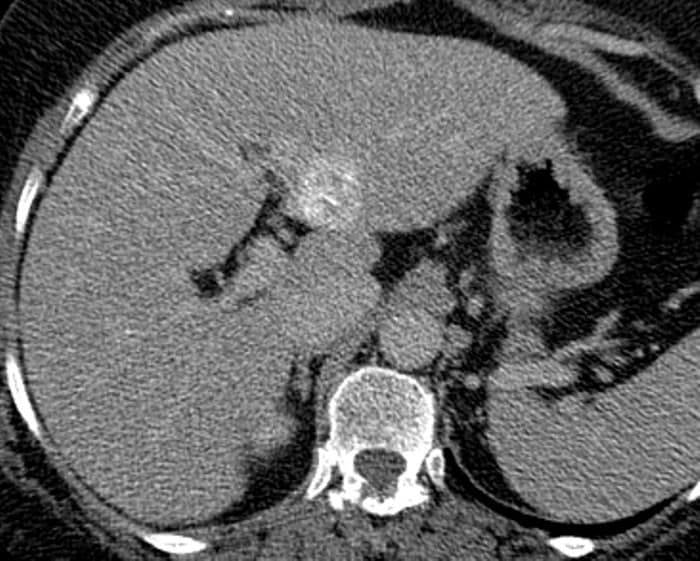

Ung thư đường mật

Ung thư đường mật - Ảnh 5

» Thông tin: Nữ giới – 56 tuổi.

» Lâm sàng: Viêm gan C.